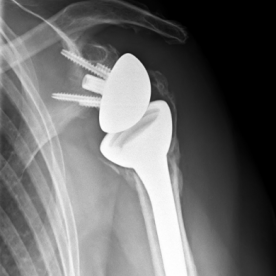

Röntgenbilder